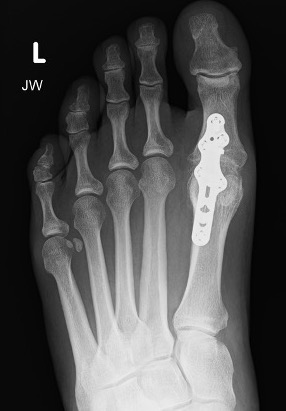

X-ray

Osteoarthritis

- joint space narrowing

- dorsomedial osteophyte

Mild to moderate OA

Severe OA

Arthrodesis

Indication

- advanced OA

- young, active patient

Screw fixation

Plate fixation

Screw + plate fixation

Fixation

- screws / plate / screws + plate